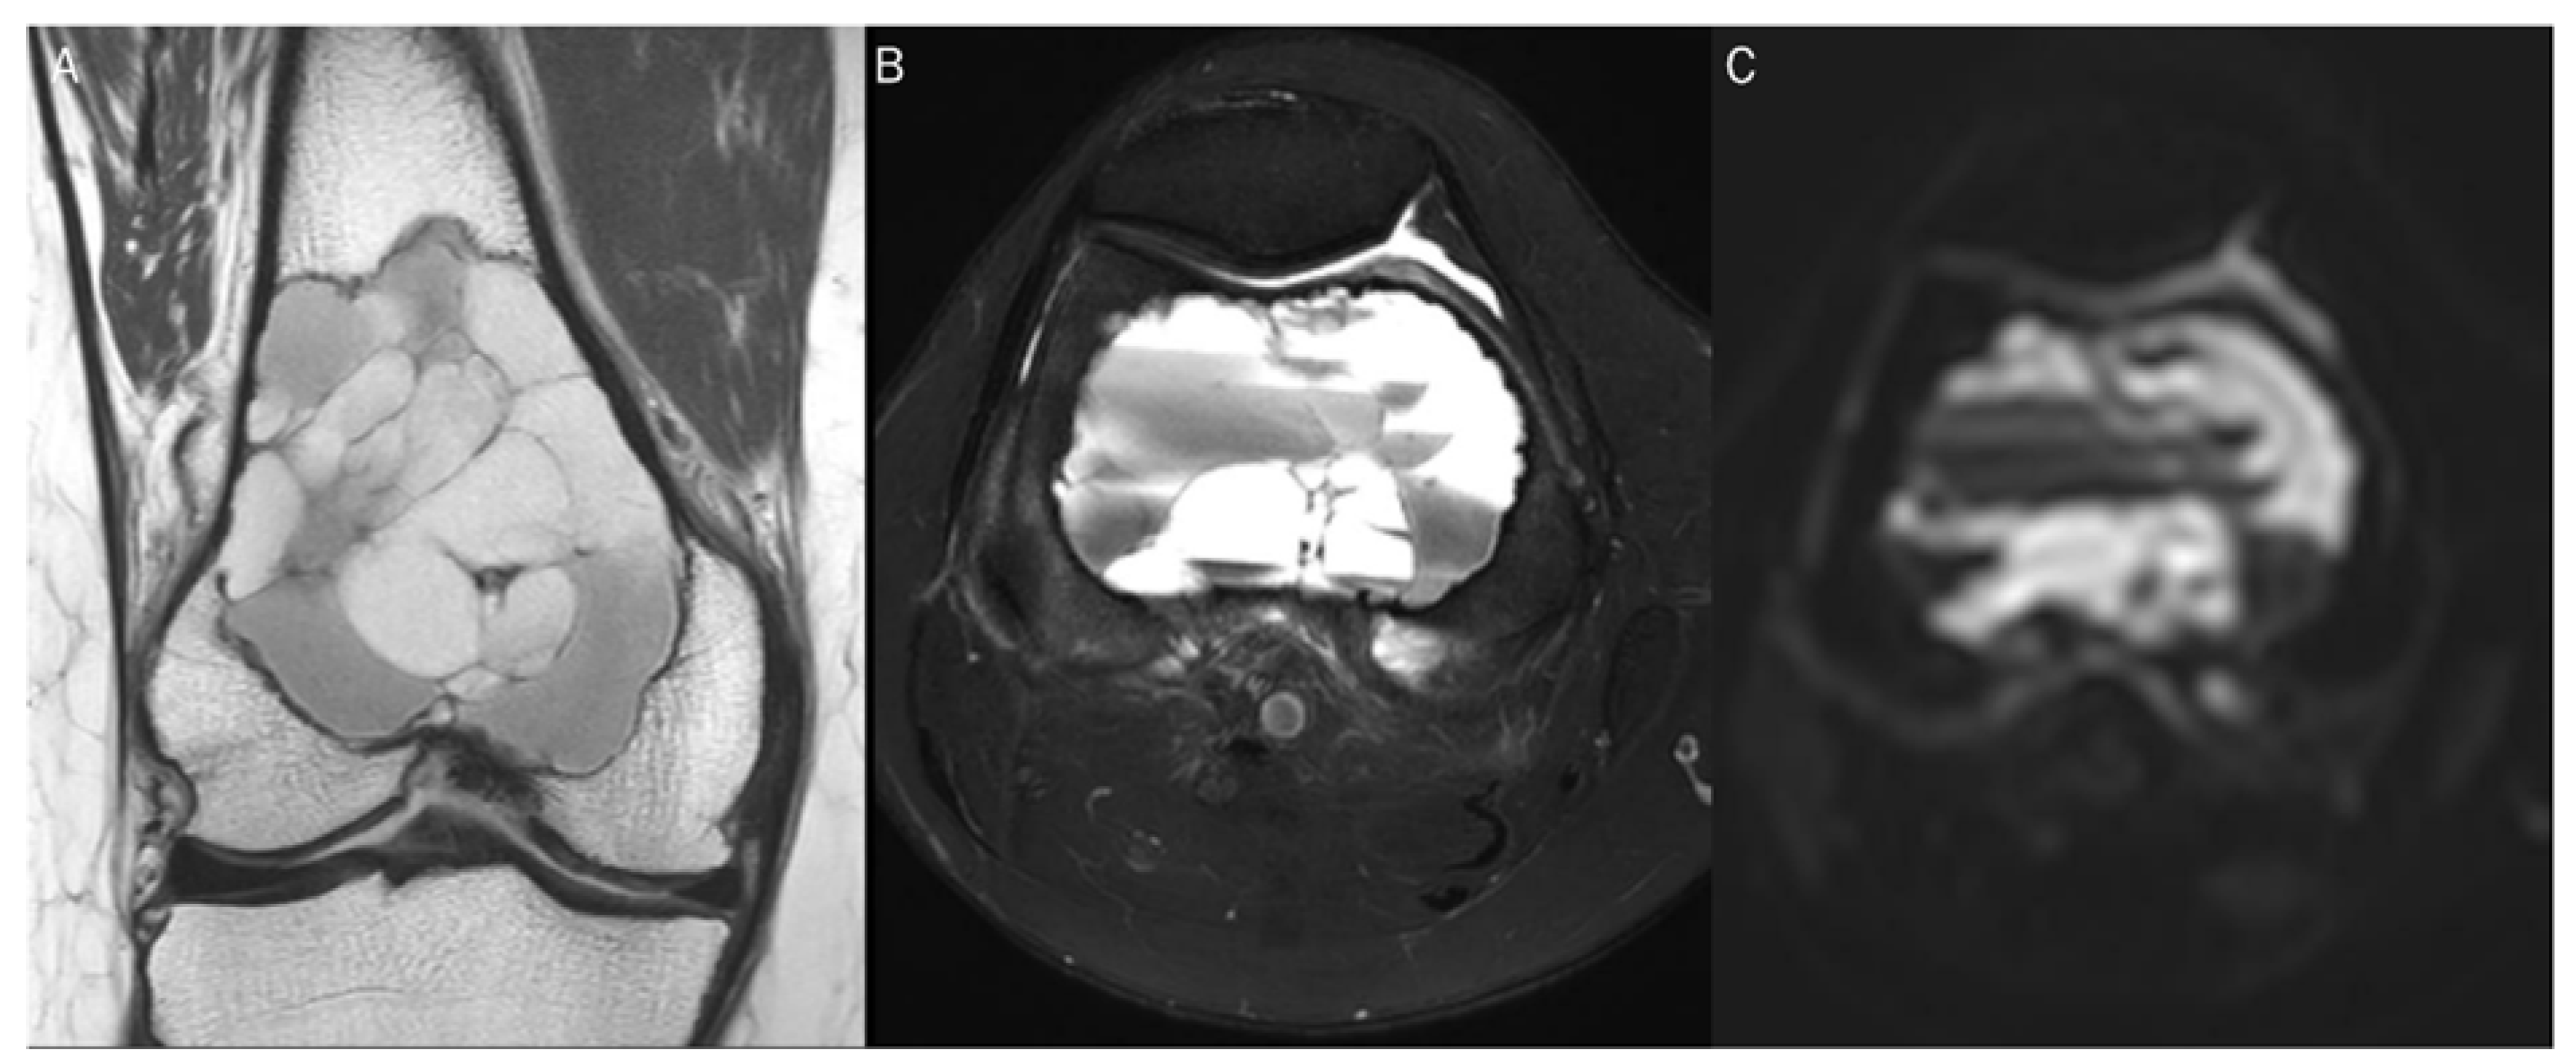

7.1. Cyst